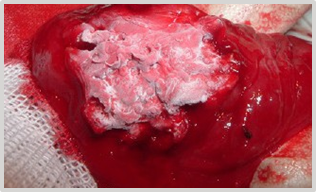

The surgical times and maneuvers from the previous cases 1 and 2 are repeated, and the tumor structure is exposed through cystotomy (Figure 28). When gently pulling and lateralizing the neoplasm, the presence of a smaller diameter circular band near the base is observed (Figure 29).

Figure 28 Prior to laparotomy and cystotomy, the tumor mass is exposed.

Figure 29 Externalization of the tumor mass, visible circular area of smaller diameter.

With the free edge of the 4mm circular electrode in a current of cutting and coagulation at an intensity of 3.8 MHz, a total transversal electrodiathermy is performed at that level. A residual area of approximately 1mm near the base-mucosa is preserved. The central area, which has a more compact consistency, is laminated. Larger diameter vessels are clamped and electrocoagulated. Microcapillary electrohemostasis is completed with a 2mm sphere electrode D3-4, at a similar frequency (Figures 30–32).

The entire material is sent for histopathological analysis (Figure 34) (Figure 35), diagnosis: fibrosarcoma.

Figure 34 Longitudinal section of the material submitted to visualize the structure.